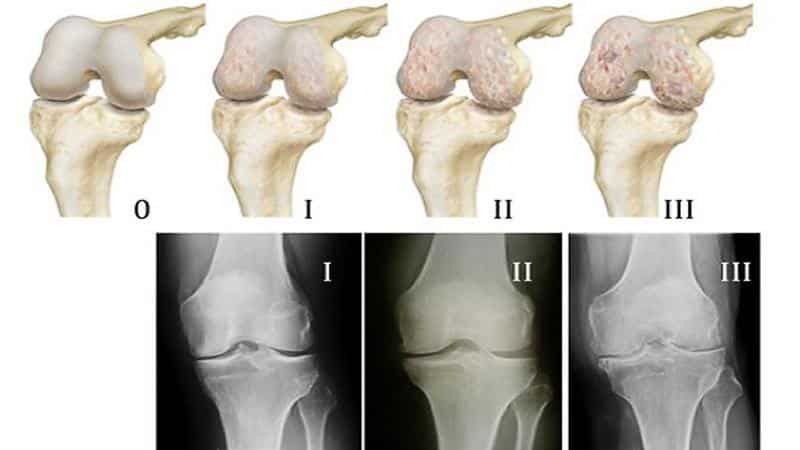

Артрозы представляют собой хронические заболевания суставов и окружающих их структур, включая околосуставные мышцы, сумки и связки суставного хряща. На первой стадии артроза происходит повреждение протеогликанов, которые отвечают за удержание влаги в хряще. В результате хрящ теряет свою упругость и эластичность, начинает «подсыхать». Коллагеновые волокна утрачивают прочность, что приводит к образованию шероховатостей и неровностей на суставной поверхности, которая покрывается трещинами.

На второй стадии артроза кости, лишенные хрящевого амортизатора, начинают сплющиваться, что приводит к увеличению суставной площадки. Вдоль ее краев формируются остеофиты — перерожденная костная ткань. Также наблюдается сморщивание патологически измененной капсулы сустава и синовиальной оболочки. Из-за нарушений в циркуляции суставной жидкости она становится более вязкой и хуже снабжает хрящ питательными веществами, что ускоряет его разрушение на 50—70%.

Когда кости теряют как смазочную суставную жидкость, так и хрящевой амортизатор, они начинают тереться друг о друга при движении. Это приводит к третьей стадии артроза, когда суставная щель практически исчезает, и дальнейшая работа сустава становится невозможной.

- Рентгенография. Это основной метод диагностики гонартроза, хотя на начальной стадии он может не показать патологию. На второй стадии можно увидеть остеофиты, участки окостенения и сужение суставной щели.